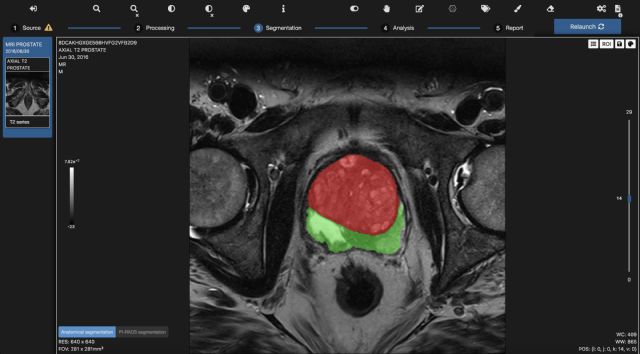

A través de sus paneles de biomarcadores de imágenes, Quibim analiza los mecanismos de enfermedades como el cáncer, mejora los programas de medicamentos y monitorea la eficacia del tratamiento. Todo ello a través de un enfoque de análisis del cuerpo completo para cada paciente, impulsando la medicina de precisión agnóstica de tejidos, es decir independientemente del tipo de cáncer o en qué parte del cuerpo se originó. Sus soluciones, QP Prostate® y QP Brain®, tienen la capacidad de detectar enfermedades de la próstata y el cerebro comparando nuevas imágenes con imágenes similares de una base de datos propia con diagnósticos ya establecidos.